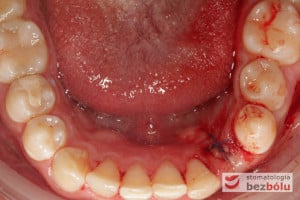

Procedurę chirurgiczną rozpoczęto od sprawdzenia przylegania szablonów do zębów pacjenta oraz znieczulenia miejscowego. W kolejnym kroku, przy pomocy specjalnie przeznaczonego do tego celu zestawu wierteł, wypreparowano krążki dziąsła punktowo odsłaniające kość a następnie poprzez tuleje prowadzące, z najwyższą precyzją, opracowano łoże implantu. Kulminacyjny moment zabiegu, czyli wprowadzenie wszczepów MIS C1 również odbyło się poprzez szablon, gwarantując precyzyjną lokalizację implantów. Zwieńczeniem całej procedury było przyszycie uprzednio wypreparowanych krążków śluzówkowo-okostnowych. Tuż po zabiegu, celem weryfikacji poprawnej pozycji implantów, wykonano zdjęcie ortopantomograficzne. Podczas wizyt kontrolnych, pacjent nie skarżył się na żadne dolegliwości bólowe, nie wystąpił obrzęk, a zreponowane we właściwych miejscach fragmenty dziąsła nie wykazywały oznak martwicy, co świadczyło o ich ponownym ukrwieniu i wgojeniu się. Wszystkie te przesłanki jasno wskazują na skuteczność zastosowania techniki komputerowej nawigacji w implantologii.